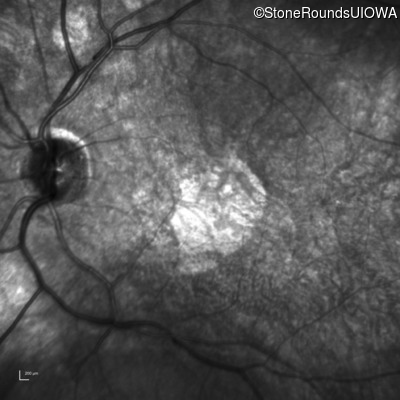

Infrared Fundus Photograph - Right - 20/100

Exemplar